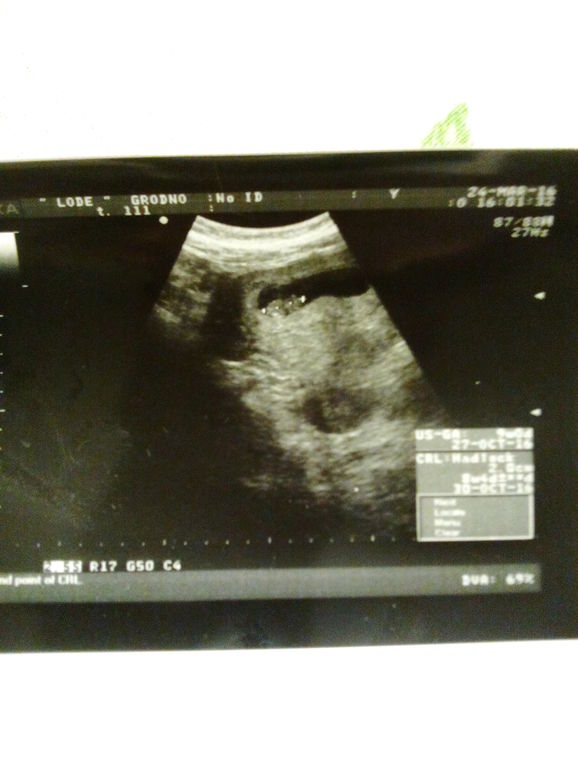

Беременность- 1 триместр ( только до 10 недель)Всем привет! Сегодня была на узи и опять вернулся тонус 2 степени. Плодное яйцо сплющенное. (Нам сегодня 9 недель.) Выписывалась из больницы, так все было хорошо, а тут неделя прошла и опять. В больнице кололи папаверин 2 р. в день. Я приехала домой - уколола 1 ампулу, а потом подумала , может надо половину??? В инструкции написано от 10 до 40 мг, в ампуле 40. Как вы кололи? Если получиться то забегу завтра к гине.